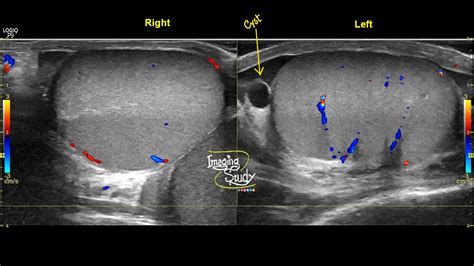

An ultrasound allows the physician to clearly distinguish between a solid mass—which requires further investigation—and a fluid-filled cyst, which is typically benign. If you have been looking for Testicular Cyst Images, you have likely seen ultrasound depictions showing dark, well-defined areas; these represent the fluid within the cyst, contrasting with the more textured appearance of the testicle itself.

When searching for Testicular Cyst Images, you will likely encounter various medical illustrations and ultrasound scans that depict these fluid-filled sacs. It is important to distinguish between different types of scrotal masses to understand why clinical evaluation is crucial: